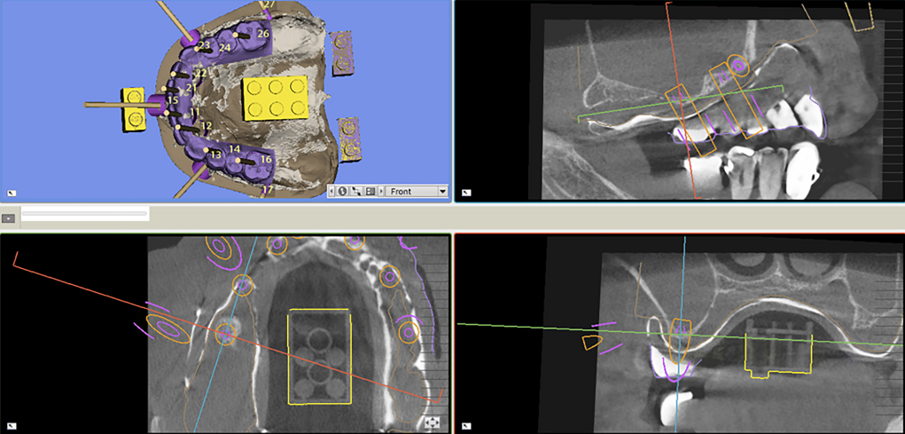

Dopo la rimozione dei denti residui e degli impianti, il paziente è stato immediatamente riabilitato con due protesi totali rimovibili diagnostiche in RP, che hanno migliorato i rapporti intermascellari, la VDO, OB, OJ, fonetica ed estetica. È stato eseguito un tracciato cefalometrico su una radiografia laterale del cranio per una valutazione funzionale iniziale del caso, seguita da una pianificazione protesica virtuale (Fig. 4), quindi radiologica (Fig. 5) e chirurgica. Le caratteristiche delle protesi studiate hanno determinato la pianificazione chirurgica (Smop, SwissMeda) (Fig. 6) e due guide chirurgiche sono state successivamente sinterizzate al laser (2Ingis) (Fig. 7). Gli impianti sono stati quindi posizionati come programmato (Figg. 8, 9), ad eccezione di quelli ai mascellari posteriori, dove è stato eseguito bilateralmente un grande rialzo del seno mascellare (Fig. 10).